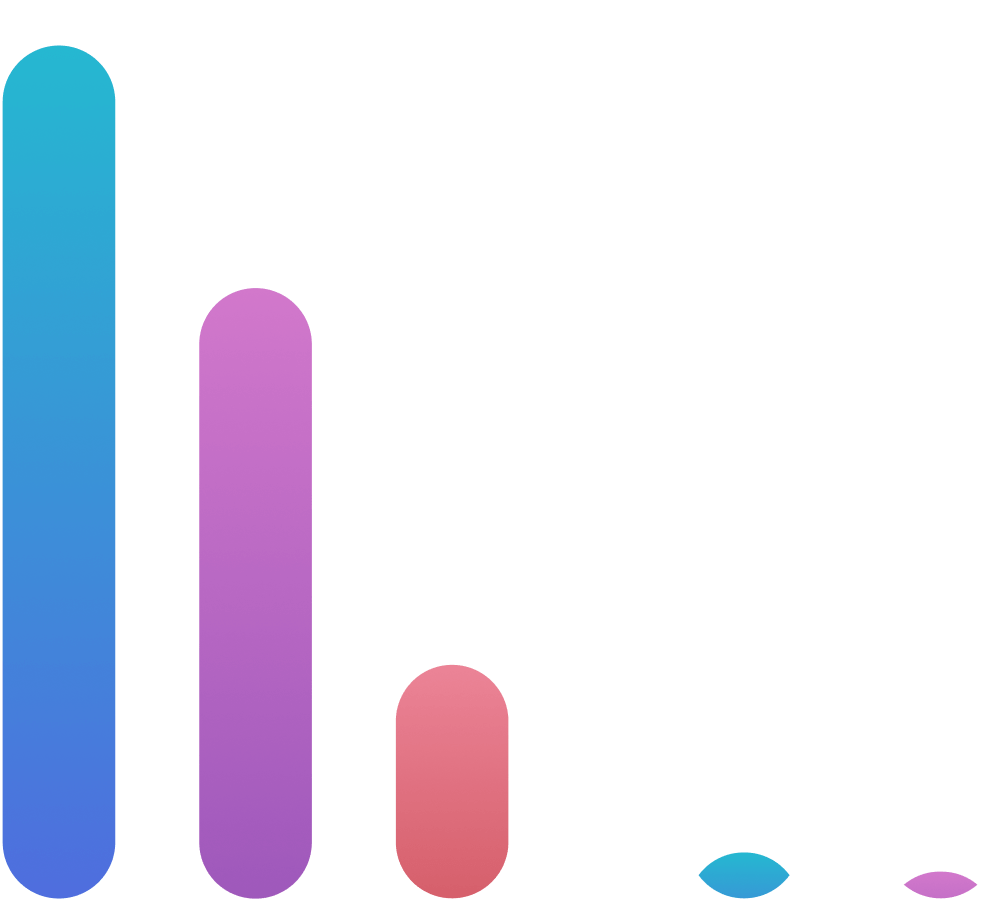

NB! Учет риска развития антибиотикорезистентности при выборе терапии, особенно при рецидивирующих ИМП

(доступные)

(контролируемые)

(резервные)

Фосфомицин

(перорально)

(доступные)

(контролируемые)

Фосфомицин

(перорально)

(резервные)